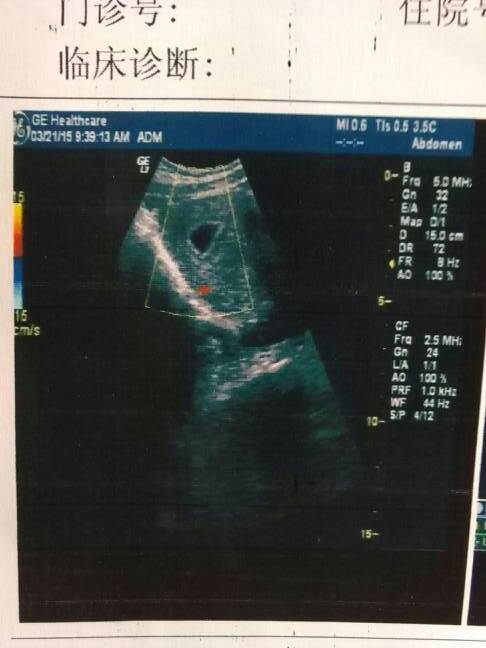

超声所见: 子宫前位,宫体大小为71×61×45mm,形态规则,轮廓清晰,实质回声均匀,宫腔内探及一14×9mm的孕囊声像,内可见卵黄囊,暂未见明显胚芽及原始心管搏动。CDFI:孕囊周边可见丰富的血流信号。诊断提示:宫内早孕,内可见卵黄囊,暂未见明显胚芽及原始心管搏动。建议复查。请问这样正常吗?孕四周。